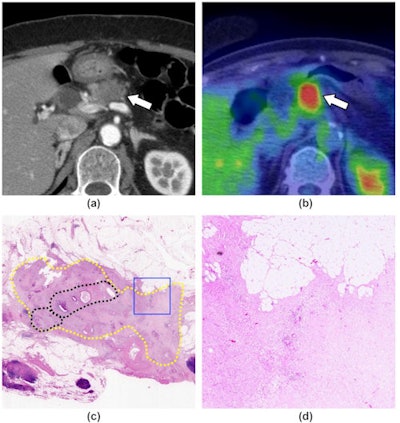

Japanese researchers analyzed imaging data from a group of patients with pancreatic adenocarcinoma who underwent F-18 FDG-PET/CT scans. They found PET radiotracer uptake values identified which patients were more likely to respond to initial chemotherapy prior to surgery.

In this retrospective study, Nishie and colleagues identified patients with pancreatic cancer who underwent F-18 FDG-PET/CT scans between April 2018 and August 2020 at their hospital. They included 28 patients who had surgery to remove tumors after initial neoadjuvant chemotherapy. Patients were split into groups of responders and nonresponders based on laboratory biopsy findings.

Next, the researchers measured maximum standardized uptake values (SUVmax) of the tumors on F-18 FDG-PET and compared the values among responders and nonresponders. The diagnostic performance of SUVmax in distinguishing between the two groups was evaluated using receiver operating characteristic (ROC) analysis.

The nonresponse group consisted of 23 cases, while the response group included five cases, according to the findings. The researchers found that the mean SUVmax of the response group was higher than that of the nonresponse group (9.00 vs. 4.26; p < 0.001). The optimal cutoff value of SUVmax was 9.28 for distinguishing between the two groups.

In addition, ROC analysis revealed that F-18 FDG-PET/CT SUVmax has a sensitivity of 80%, a specificity of 95.7%, and accuracy of 92.9% when predicting patients in the response group.